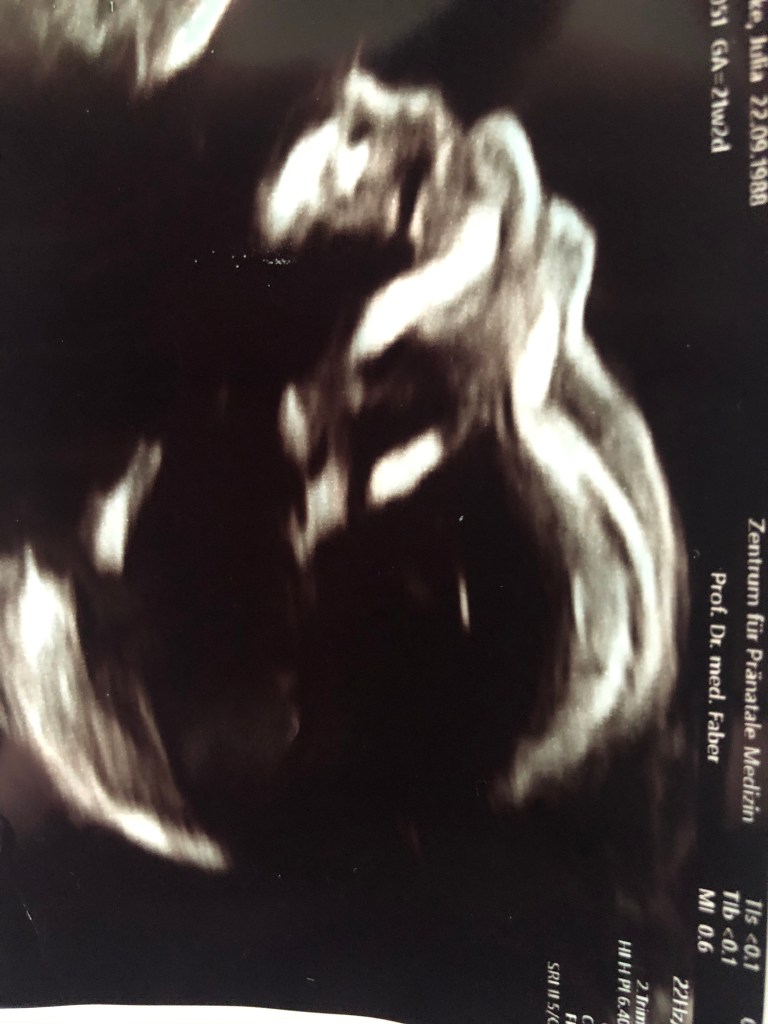

Bei der 2. Untersuchung 4 Wochen später schaute mein Arzt ziemlich lange auf den Bildschirm. Irgendwie klopfte plötzlich mein Herz bis zum Hals. Warum? Reden sie doch mit mir, schoss mir durch den Kopf. Leni hatten wir bis Dato immer noch nichts gesagt, wir haben uns dazu entschlossen, die ersten Wochen abzuwarten. Dem Arzt fiel auf, dass unser kleiner Frosch nicht gewachsen ist. „Das Baby ist viel zu klein für diese Woche.. Mir rollten die ersten Tränen über das Gesicht. „Machen sie sich vorerst mal keine Sorgen“ sagte er und streichelte dabei über meinen Arm. Nach meinem Termin, lief ich aus der Praxis, mit tausend Gedanken in meinem Kopf. Wie soll ich mich jetzt gegenüber Tobias und meiner Familie verhalten? Sollte ich erst einmal alles für mich behalten? Brauche ich aber vielleicht jemanden zum reden? Ich entschloss mich dazu die Kirche im Dorf zu lassen und verdrängte es in meinen Hinterkopf. Ich streichelte über meine kleine Kuller und sagte immer wieder: „wir schaffen das“ und genau so sollte es auch sein. 4 Wochen später zum nächsten Termin hatte der kleine Frosch aufgeholt, aber wie! Plötzlich waren wir wieder voll in den Wochen drin. Größe und Gewicht waren super. Der Arzt war zufrieden und ich beruhigt. Doch was war vorher in der Zeit passiert, als er nicht mehr gewachsen ist? Darüber machte ich mir keine Gedanken. Jetzt wissen wir, was der kleine Frosch getrieben hat in der Zeit. Meine Schwangerschaft verlief ab da an blendend, ich fühlte mich wohl, ich fühlte mich schön, ich war rundum zufrieden. Als der Bauch dann richtig wuchs, kauften wir Leni ein T-Shirt, auf dem stand: •ich werde eine große Schwester•.. sie war so glücklich, ihre Augen strahlten, plötzlich sagte sie klar heraus: „aber ich nehme nur eine Schwester..“ oh,dachte ich, das kann ja noch lustig werden.😊 Leni verriet nun überall, dass sie große Schwester wird. Niedlich! Sie war sooo stolz. Wir freuten uns alle, bis der Tag der Feindiagnostik kam..